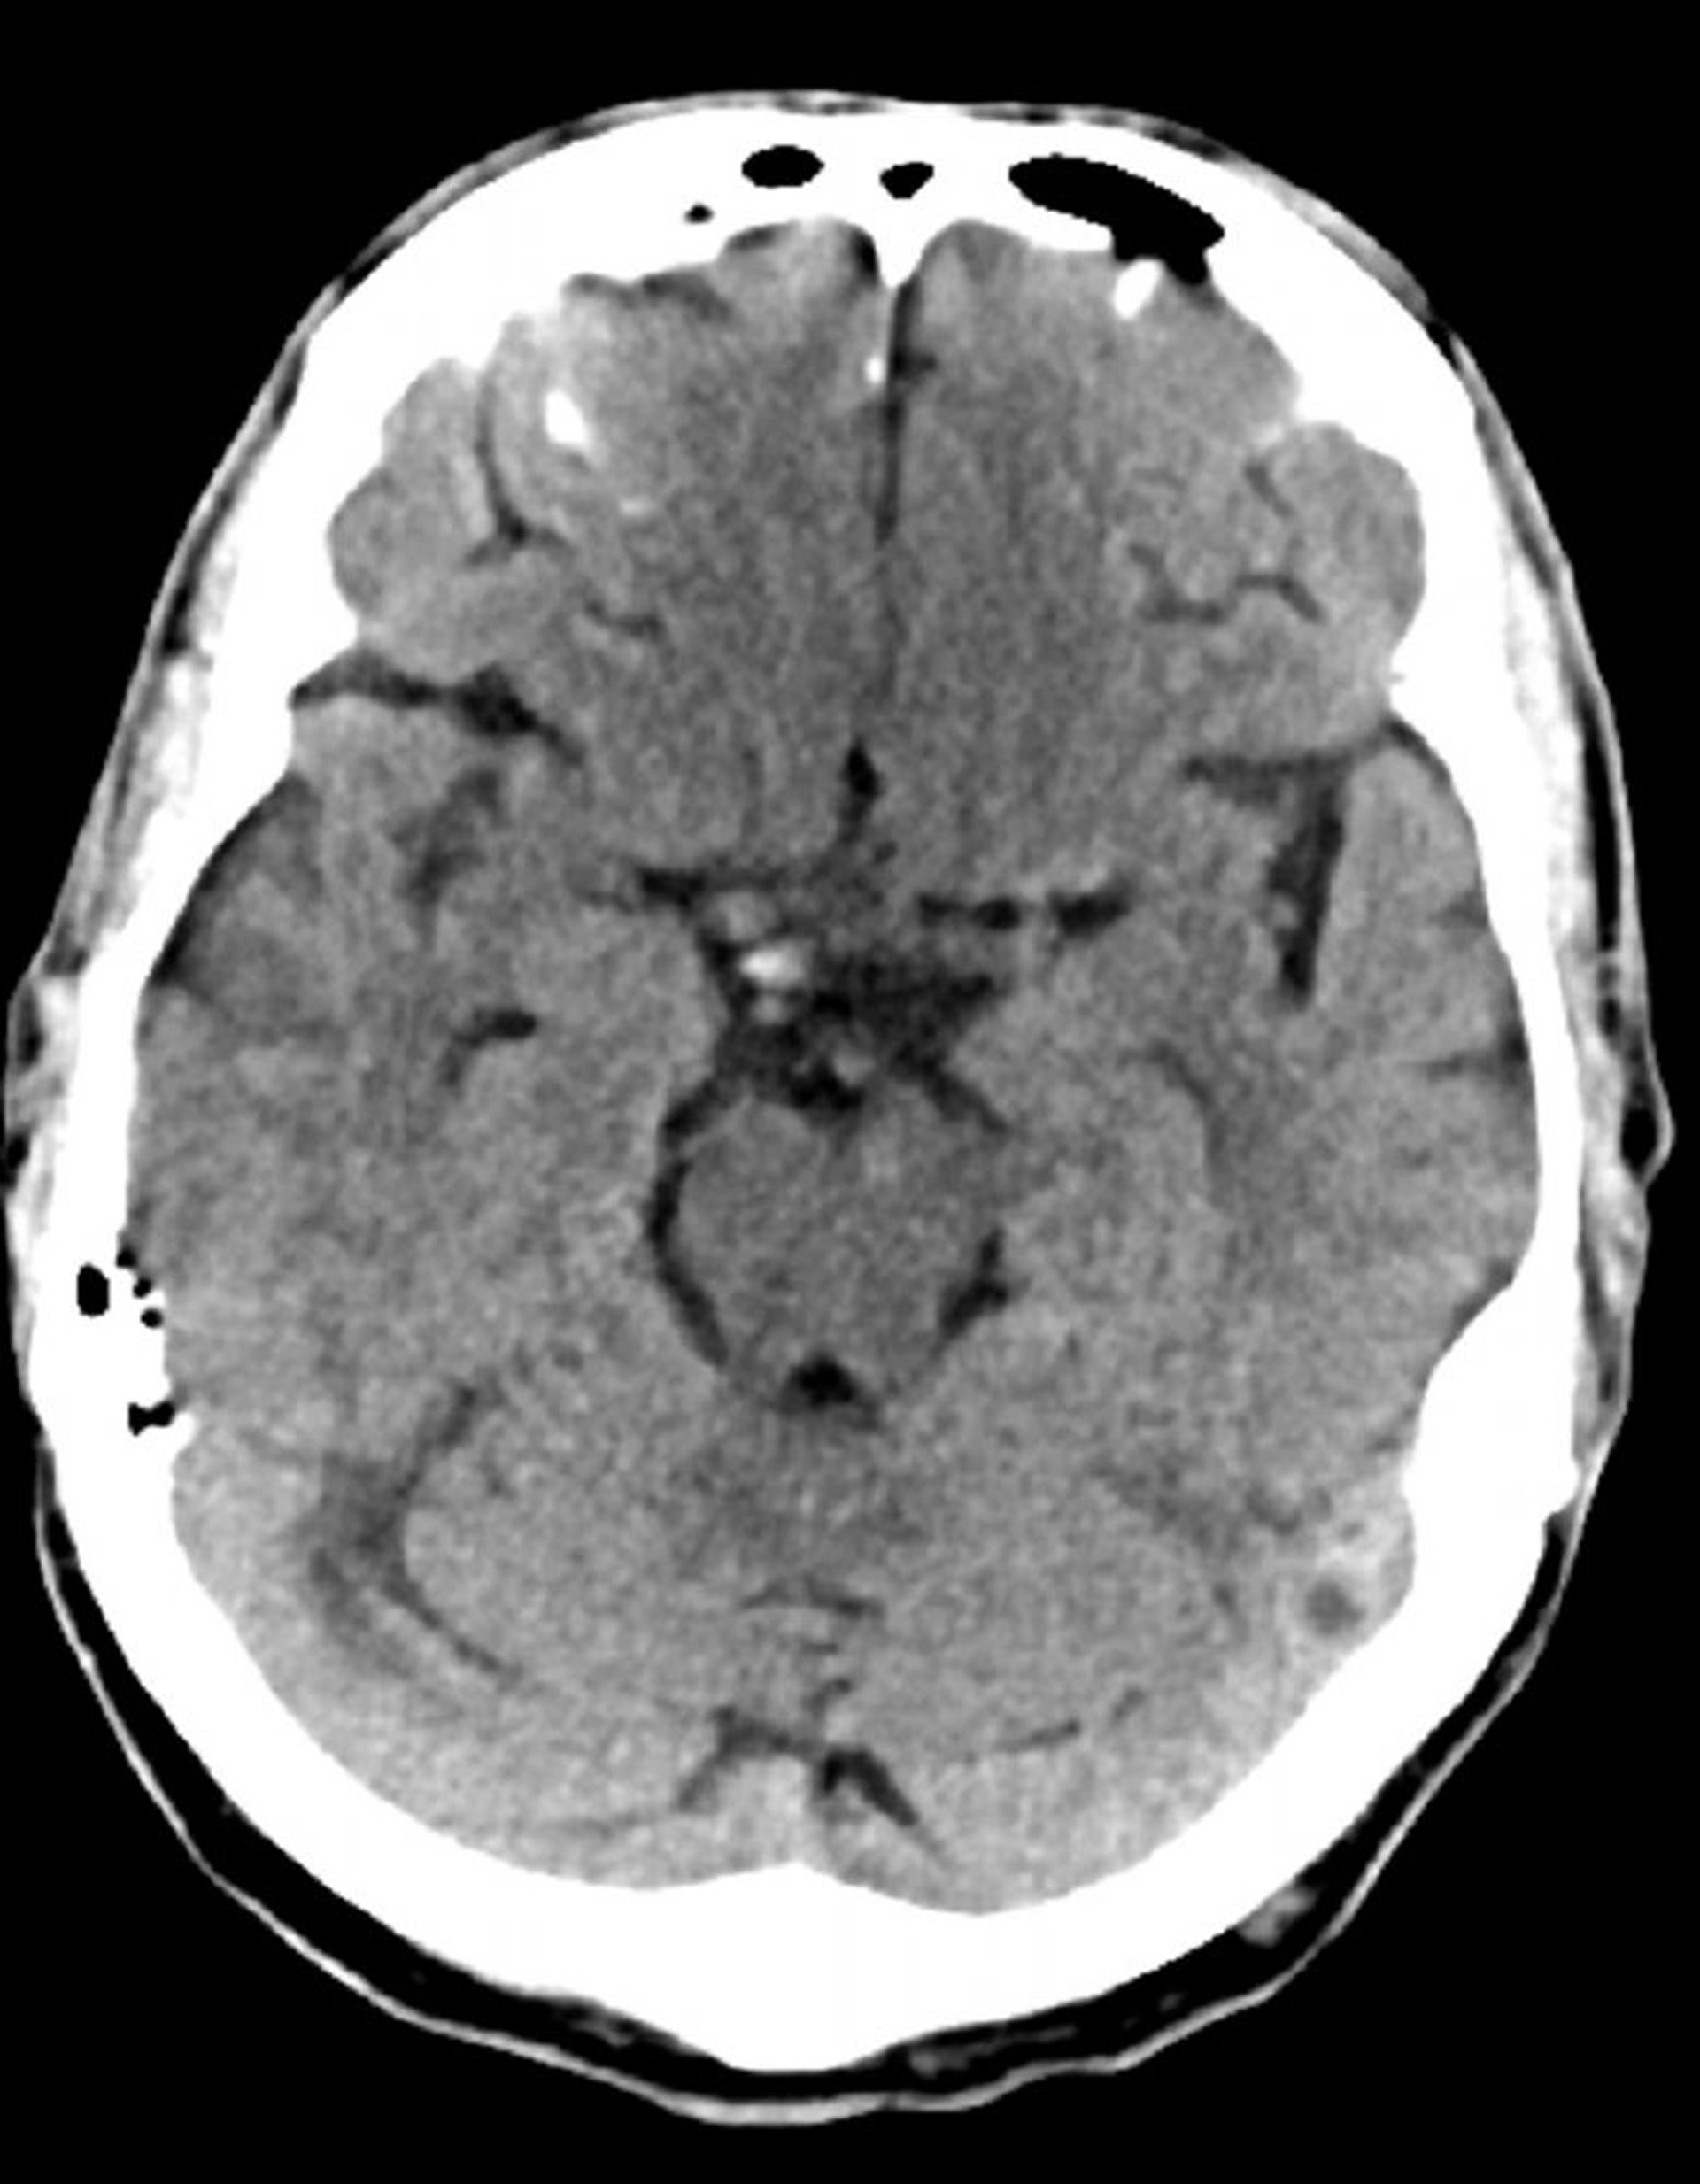

TC cerebrale normale (adulto di 74 anni), slide 7

Questa immagine è una normale TC della testa di un adulto di 74 anni. Rispetto alla normale TC della testa di un soggetto di 30 anni, i ventricoli e i solchi sono più grandi. Questi reperti sono normali in questa fascia d'età.